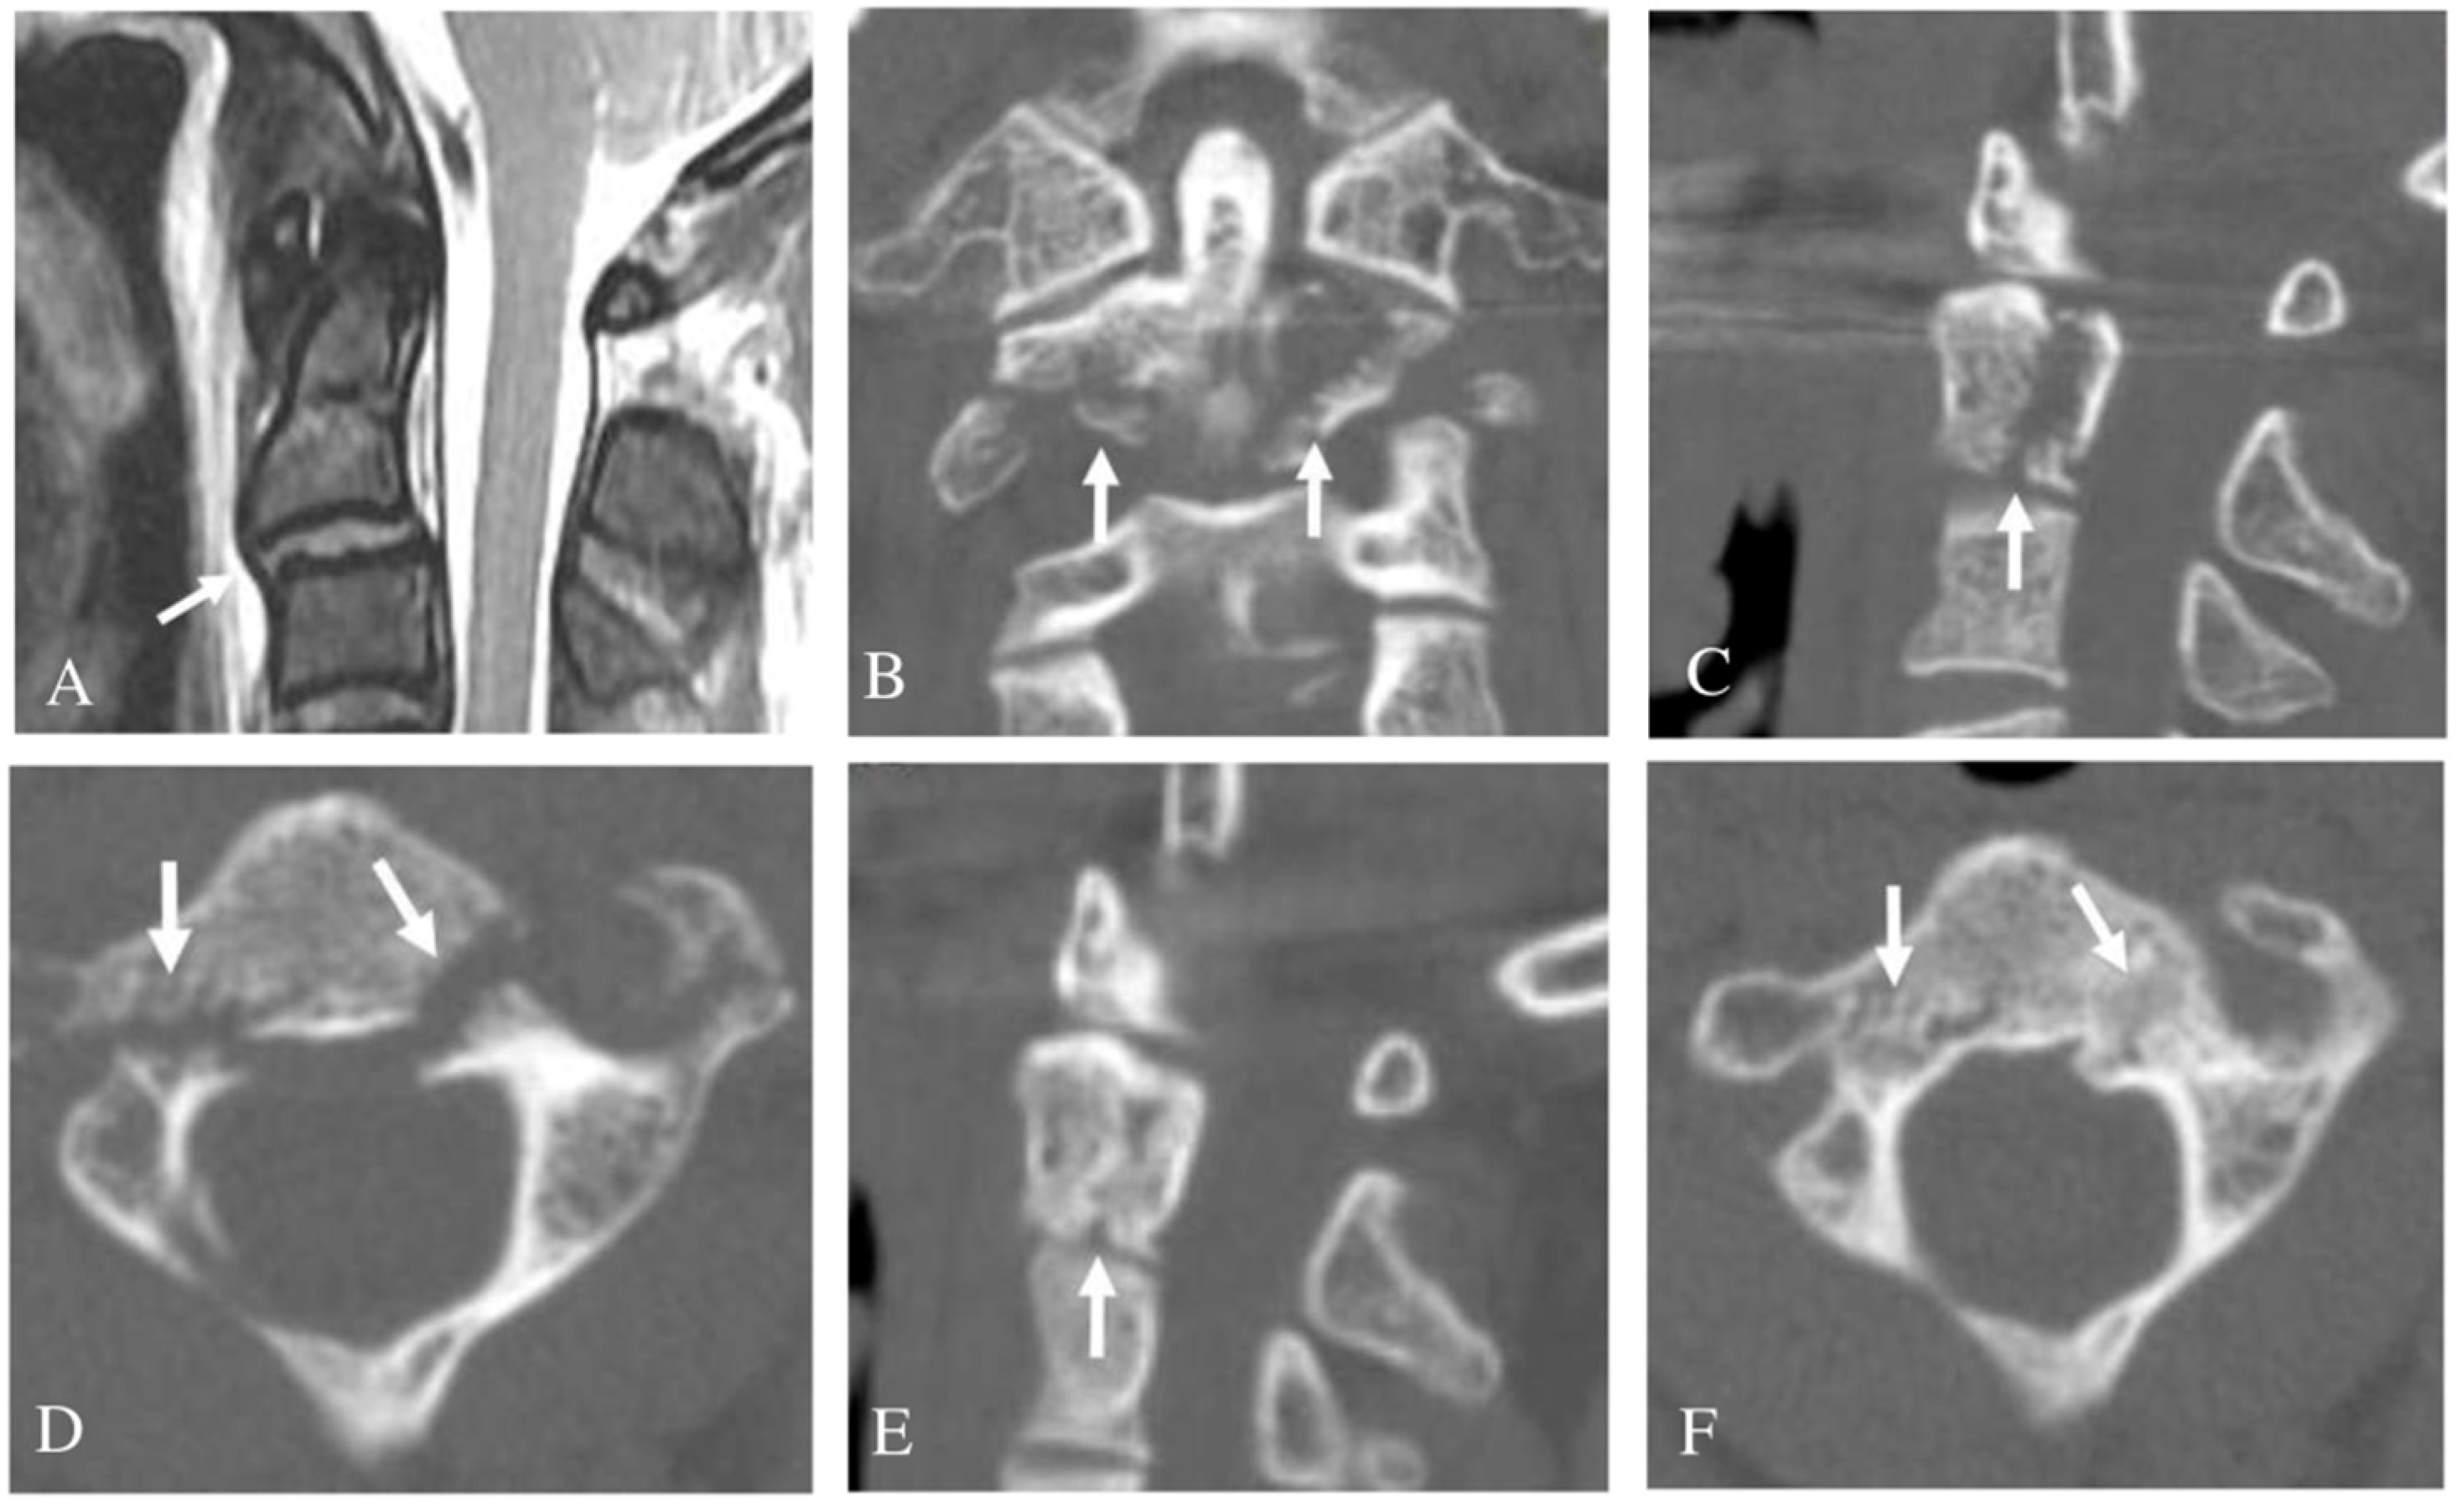

3.3. Bilateral Pedicle Fracture